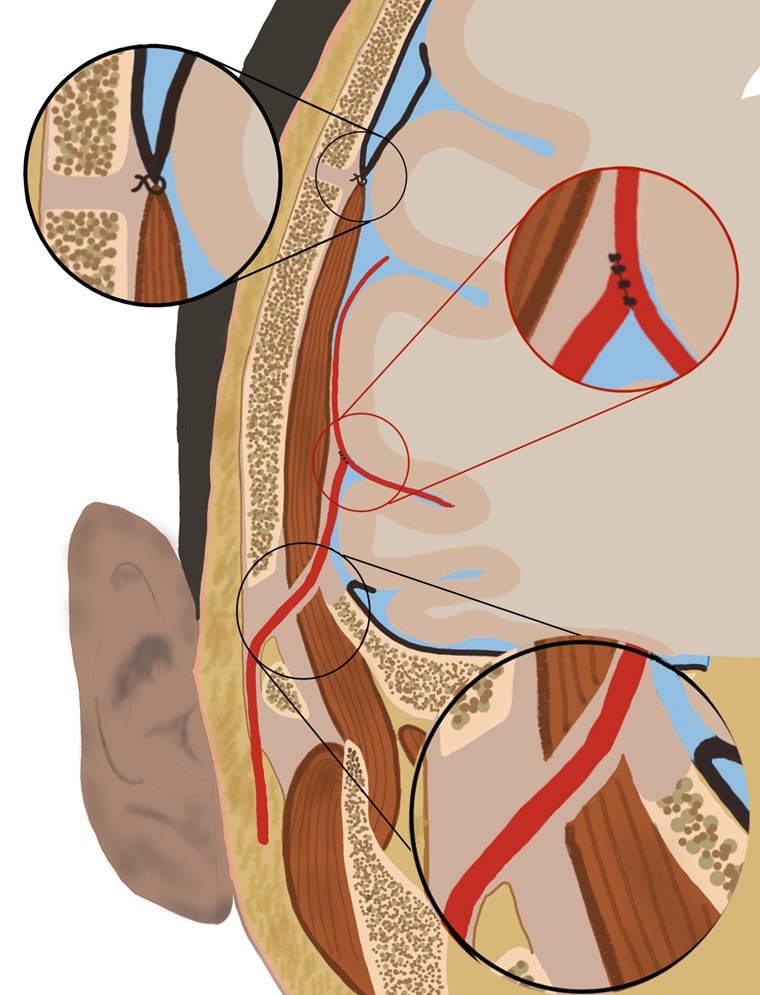

There are two types of surgery advocated in Moyamoya angiopathy.

Direct revascularization surgery (Brain bypass surgery)

A tiny blood vessel from the scalp is harvested and surgically connected to a blood vessel in the brain. This surgery allows blood to bypass the obstruction in the internal carotid artery and reach the brain. This technically demanding surgery is always done in combination with the indirect revascularization surgery (below).

Indirect revascularization surgery

Tissues in the vicinity of the brain such as the muscle (temporalis muscle), dura (covering membrane of the brain) and galea (scalp tissue) are surgically attached to the brain surface. New blood vessels sprout from these tissues to supply the oxygen-starved brain.